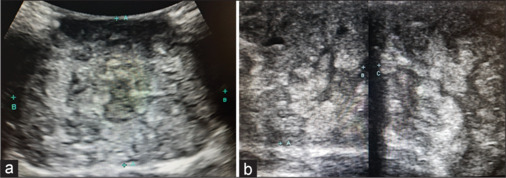

Hamartoma of the breast is a rare benign lesion that leads to unilateral breast enlargement with evidence of a localized palpable mass. Ultrasonography findings are typical and include a well-defined mass lesion of heterogeneous echotexture consisting of mixed echogenic and sonolucent areas. This case report describes a hamartoma of the breast in a 17-year-old female.

乳房错构瘤是一种罕见的良性病变,可导致单侧乳房增大,伴有局部可触及的肿块。超声检查结果是典型的,包括一个明确的肿块,回声质地不均匀,由混合的回声和透光区域组成。本病例报告描述了一名17岁女性的乳房错构瘤。